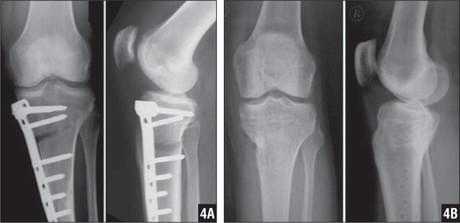

Пациент М. 1980 г.р., травму получил при падении на стопы с высоты 1,5 метра. Лечился по месту жительства (в травмпункте районной больницы) консервативно в гипсовой повязке в течение 14 дней. Консультирован в травматологическом отделении ФГБУ «УНИИТО им. В.Д. Чаклина» Минздрава РФ, предложено оперативное лечение. При поступлении кожные покровы стопы чистые, без признаков воспаления и сдавления тканей. Стопа отечна, уплощена. На рис. 1 представлены рентгенограммы пациента. Прооперирован через 2 недели после травмы. Операция состоит из двух этапов. Первый этап заключается в наложении дистракционного аппарата. Проводятся две спицы 1,8 мм во фронтальной плоскости: первая через нижнюю треть диафиза большеберцовой кости, вторая через бугор пяточной кости (рис. 2). Спицы фиксируются в дистракционном аппарате, выполненном из двух полуколец, соединенных между собой двумя телескопическими тягами. Особое расположение полуколец, фиксация спиц на концах полуколец, крепление кронштейнов для телескопических тяг обеспечивает тракцию пяточной кости в необходимом направлении с использованием минимального количества спиц и внешних опор при сохранении необходимого поля обзора для проведения рентгенологического и визуального контроля репозиции и фиксации. Второй этап - закрытая элевация импрессированной суставной поверхности и окончательная репозиция пяточной кости. Через разрез длиной до 1 см по латеральному краю ахиллова сухожилия (рис. 3) в месте его прикрепления к пяточной кости под соответствующий фрагмент подводится элеватор (рис. 4), манипуляцией которым устраняется смещение и выполняется провизорная фиксация спицами 1,5 мм (рис. 5). При сагиттальном раскалывании суставной фасетки целесообразно проведение одного-двух винтов субхондрально (рис. 6). Стержень вводится с дорзальной поверхности пяточной кости по ее оси через разрез до 2 см по предварительно сформированному остеотомом каналу (рис. 7, 8). Далее через проколы кожи с помощью кондуктора (рис. 9) выполняется запирание винтами с латеральной поверхности, внешнее устройство демонтируется. Достигнуто удовлетворительное стояние отломков (рис. 10).

Рис. 1. На рентгенограмме левой стопы в прямой и боковой проекциях определяется оскольчатый внутрисуставной перелом левой пяточной кости

Рис. 2. Первый этап оперативного лечения - наложение дистракционного аппарата